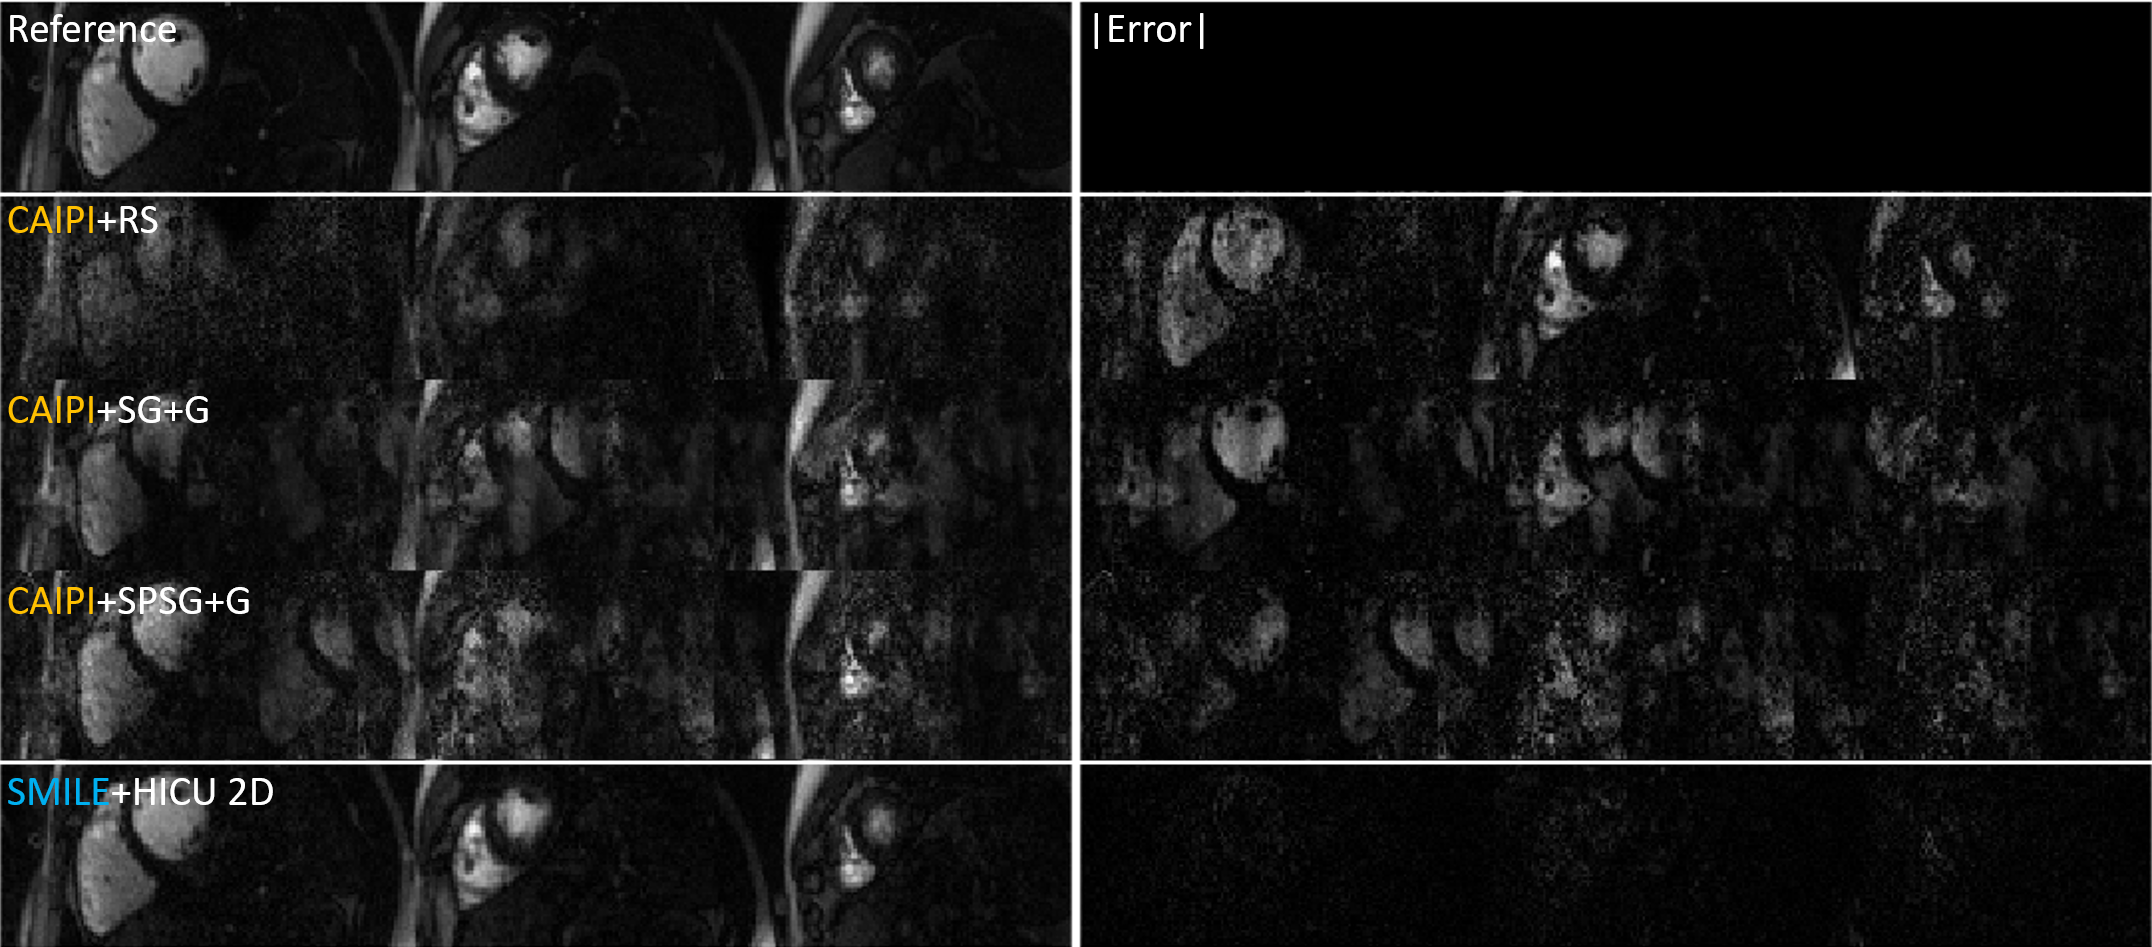

Fig. 4 and Fig. 5 show the representative reconstruction and absolute value of error map, we can see that the CAPI + existing state-of-art methods show inferior image quality as compared to SMILE + reconstruction methods, where the slice leakage from other slices is more easily observed in the absolute error map in the CAPI results.

Figure 4: Representative retrospective result for MB=3, R=6 the absolute error is scaled by 1.24.

Refer to caption

Figure 5: Representative retrospective result for MB=5, R = 5, the absolute error is scaled by 1.71.